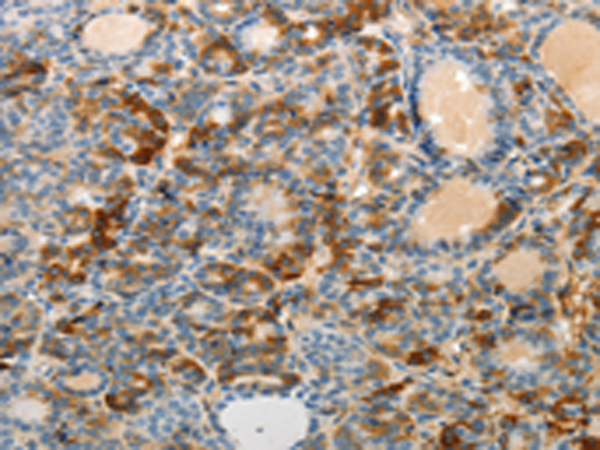

分类: 科研抗体货号: P07409别名: ARM1; EMSP; PSTS; AI2A1; EMSP1; KLK-L1; PRSS17; kallikrein应用: IHC反应种属: Human